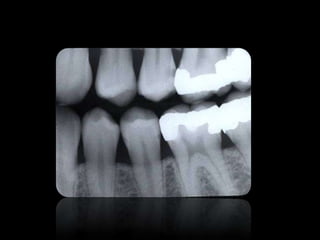

CARIES

ABSCESO PERIAPICAL